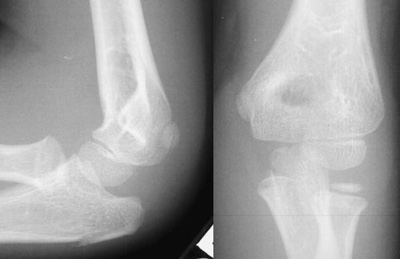

Look for obvious fracture lines and subtle disruptions in cortical contour.

This is not a good lateral radiograph so interpretation of the anterior humeral line is unreliable. There is no obvious anterior or posterior fat pad, and the radio-capitellar line is intact. The radial head and distal humerus appear fine, while there is an obvious proximal olecranon fracture.